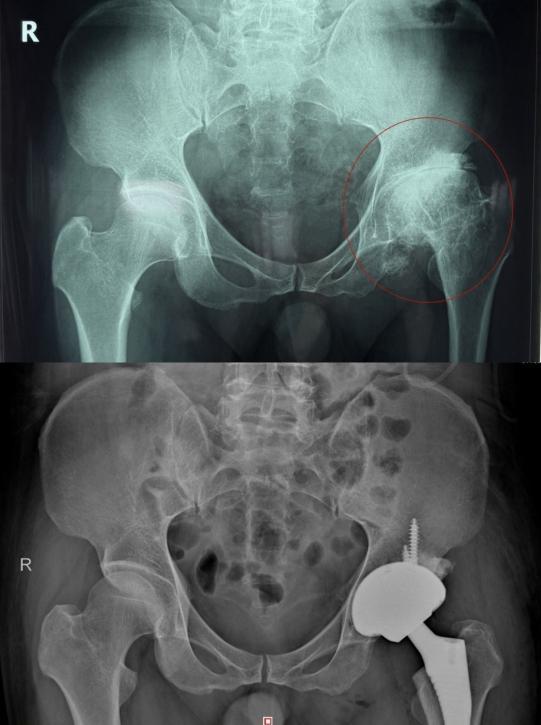

家住益阳的52岁杨先生左髋部反复疼痛20余年,近期疼痛加剧、关节活动严重受限,就医确诊为股骨头坏死晚期,近日在湖南省第二人民医院(省脑科医院)骨关节运动医学科,接受全髋关节置换手术才得以缓解,目前正在进一步康复中。

(患者术前术后影像对比)

第三,晚期(塌陷严重、疼痛剧烈):全髋关节置换术是目前最成熟、效果最确切的治疗方式,术后可快速恢复行走与日常活动,生活质量显著提高。